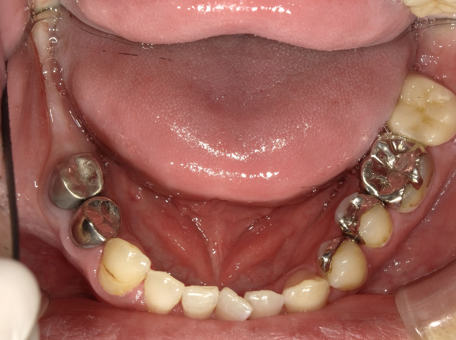

治療前

| はじめのご相談内容 | 「奥歯が割れたため歯を抜くことになったが、入れ歯は嫌なのでインプラント治療をしたい、手前の銀歯も一緒に白くしたい」とご相談いただきました。 |

| 診断結果 | 骨の状態を確認し、インプラント治療が問題なく出来ると判断しました。インプラントの上部構造として白い被せものが入る予定なので、手前の銀歯も合わせて治すことで、より上品な口元になると判断しました。 |

| 行った治療内容 | インプラントの上部構造部分はジルコニアを使った被せものにしたため、手前の銀歯も同じ素材で治す方が見た目が良くなることをご提案しました。 |